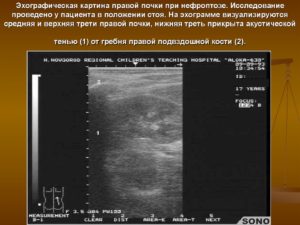

УЗИ диагностика дает возможность установить степень подвижности органа и степень его опущения.

- УЗИ почки в вертикальном и горизонтальном положении больного;